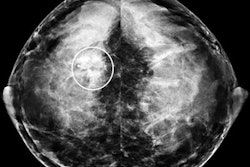

Performing a screening ultrasound exam along with mammography can yield breast cancer detection gains, but at the cost of a substantial increase in the number of false positives, according to findings from the American College of Radiology Imaging Network (ACRIN) 6666 screening ultrasound trial.

"The addition of a single screening ultrasonographic examination to mammography for women at elevated risk of breast cancer results in increased detection of breast cancers that are predominantly small and node-negative," wrote a research team led by Dr. Wendie Berg, Ph.D. (Journal of the American Medical Association, May 14, 2008, Vol. 299:18, pp. 2151-2163).

"Supplemental physician-performed screening ultrasound increases the cancer detection yield rate by 4.2 cancers per 1,000 women at elevated risk of breast cancer, as defined in this protocol (95% CI, 1.1-7.2 cancers per 1,000), on a single, prevalent screen," the authors wrote.

"Adding a single screening ultrasound to mammography will yield an additional 1.1 to 7.2 cancers per 1,000 high-risk women but will also substantially increase the number of false positives," the researchers wrote.